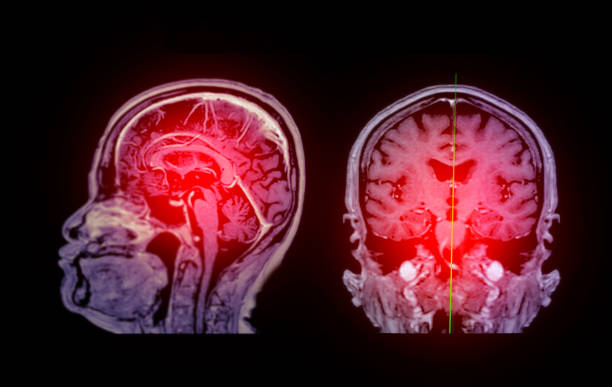

缺血性腦卒中,又稱腦梗死,是一種因腦部血液循環(huán)障礙導致的腦組織壞死疾病。它給患者帶來的不僅是身體上的痛苦,更是心理上的巨大壓力。